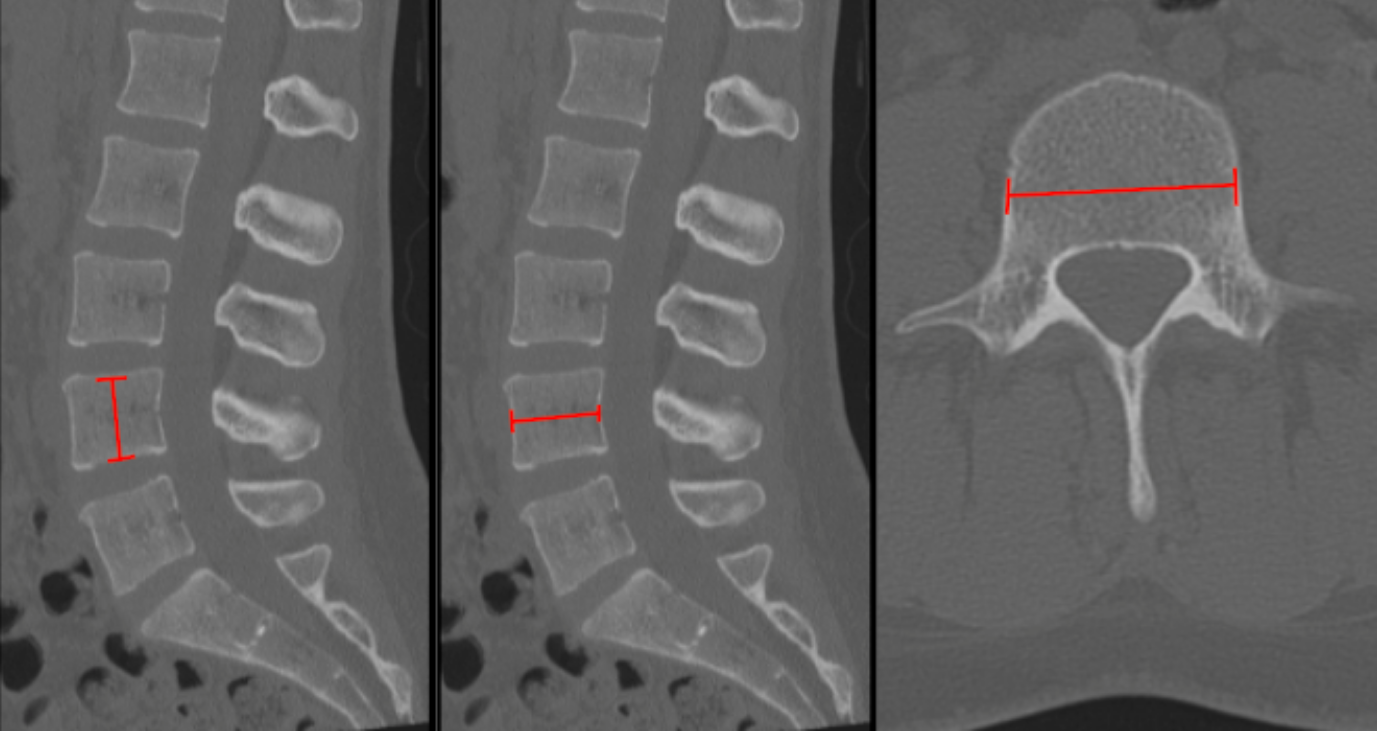

Step 2 – Vertebral Body Height (Sagittal CT)

• On a true mid-sagittal image:

• Measure from the midpoint of the superior endplate to the midpoint of the inferior endplate.

Step 3 – AP Depth (Axial or Sagittal CT)

• On Sagittal CT through the mid-vertebral body:

• Measure from the anterior cortex to posterior cortex at the midline of the vertebral body.

Step 4 – Transverse Width (Axial CT)

• On the same axial slice:

• Measure the maximum mediolateral diameter of the vertebral body between the lateral cortical margins.